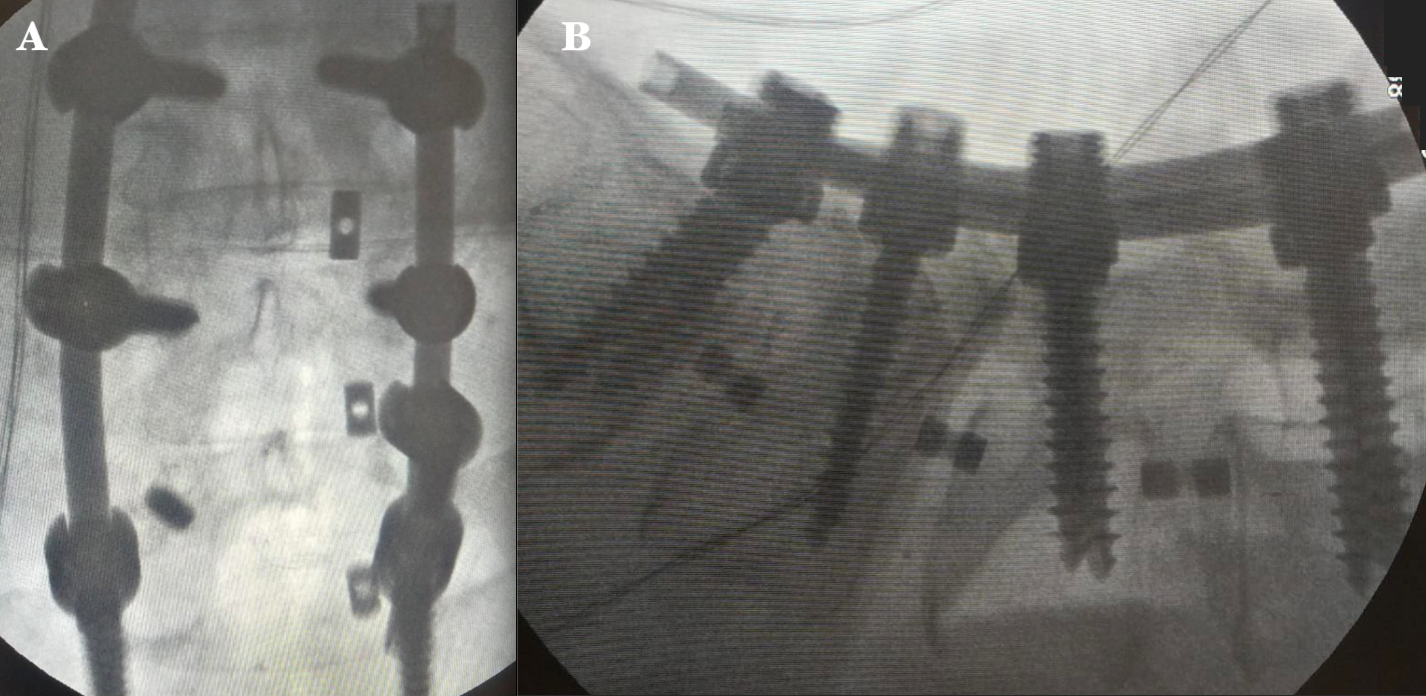

61-year-old female, with type 2 diabetes mellitus, spinal surgery in 2017 in which a discectomy and transpedicular instrumentation of L4-L5 was performed. Presented herself into the ER with a history of low back pain and related left leg symptoms which increased with lumbar flexion and extension of 8 months of evolution. Physical examination showed limp gait, left paravertebral muscular contracture, hyperesthesia, and nerve root irritation. Implant fatigue was evident (Figure 1 & 2). A standard posterior approach to lumbar spine was performed, the rods were removed, identifying the fatigue of the right L5 transpedicular screw, the polyaxial head was then removed with a plier to expose the broken screw head. Then, the rest of the screws were removed with torx screwdriver. Subsequently the interbody cages L3-S1 were inserted with TLIF technique in addition to transpedicular instrumentation (L3-L4-S1 right; L3-S1 left) (Figure 3). After surgery, the patient showed an immediate improvement, decreased pain and absence of leg symptoms. She started to walk 8 hours after the surgery, and she was discharged 20 hours later without complications.

Figure 1 Preoperative X-ray radiographs of the lumbosacral spine. A) Anteroposterior image shows transpedicular instrumentation at the L4-L5 level. B) Lateral image shows the interface area of the transpedicular screw and fatigue of the right L-5 screw..

Figure 2 Preoperative dynamic X-ray of the lumbosacral spine. A) Lateral flexion image shows L4-L5 spinal instability. B) Lateral extension image shows a decrease in the foraminal space at the L4-L5 and L5-S1 levels, with displacement of the right L5 screw due to fatigue..